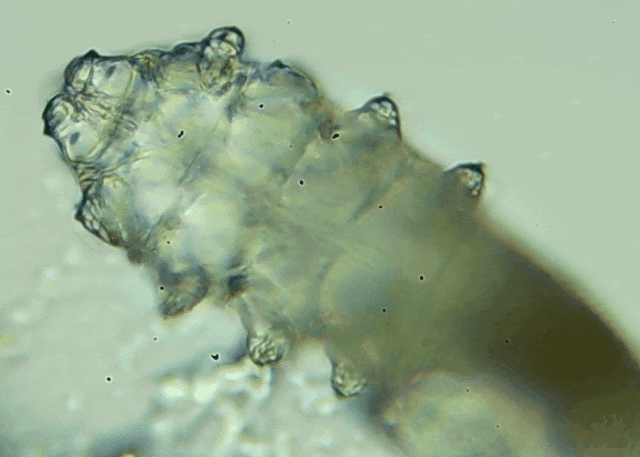

蠕形螨是一类肉眼看不见的寄生螨,常见的有毛囊蠕形螨和皮脂蠕形螨,常驻在人类的毛囊和皮脂腺里,尤其是眼睛的睑板腺和睫毛根部。数量少时,蠕形螨能与人体“和平共处”,但一旦你免疫力下降、油脂分泌旺盛或清洁不到位,他们就会以你难以想象的速度疯狂繁殖。